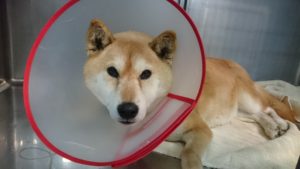

9歳の柴犬「あんず」さんです。クッションとは全く関係ありません。笑

あんずさんは、少し前から食欲が落ちてきていて、さらにここ1週間くらいで、妙にたくさん水を飲むようになったということで来院されました。

話を聞くと、避妊手術はしておらず、発情出血(人間の生理みたいなもの…厳密には違うのですが)をここ数年見ていないということでした。

外陰部を見てみると、発情してるわけでもないのに何だか腫れぼったい…。

熱も39.7℃、発熱しています。

これだけ情報があれば、獣医さんなら大抵考えることは同じでしょう。教科書に載せられるくらい典型的なパターンです。

問診は非常に優秀な検査ですね。話はいくら聞いてもタダですし。笑

エコーを見てみると、思った通り、パンパンに膨らんだ子宮が見えました。子宮蓄膿症ですね。

血液検査では、よく似た症状を出す腎臓病や糖尿病の可能性が否定され、即日入院、即日手術となりました。

ちなみに、食欲や元気の低下はどんな病気でも出る可能性がありますが、水をよく飲む・おしっこが増える、っていうのが腎臓病・糖尿病・子宮蓄膿症にわりと特徴的な症状です。

今回は、飼い主さんが認識していたのは「なんとなく食欲が落ちてる」という程度の症状でしたから、「ほっといたら死にます」と言われればそりゃあびっくりするでしょう。

その点は申し訳ないのですが、実際そうなので仕方がないのです…。

そんなわけで手術です。

終わった~!よく頑張りました!

…というわけで、無事に手術は終わり、4日後に退院しました。

ただその間も、結構お高い抗生物質とかを使って、油断なく治療しましたので、どうしても費用はかかります。全部で13万くらいかかったかな?

とはいえ、これでもあんずさんは比較的すんなり治った方でして、貧血や止血異常、免疫異常が重度だと、手術後も色々な治療を継続する必要があります。

実際さっきのあんずさんも、麻酔をかけた後、突然ものすごい徐脈(心拍数が少ないこと)になってヒヤリとしました。薬で心臓をアシストしつつの手術になりましたが、なんとかもちこたえてくれて良かった…。